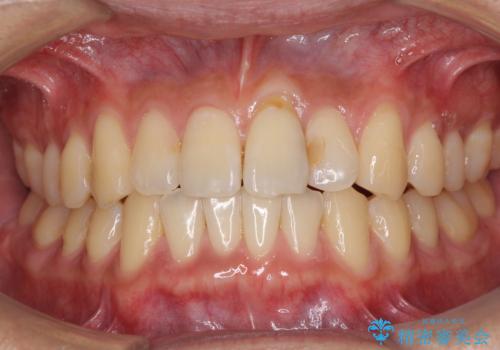

気になる前歯のデコボコをインビザラインで解消

- 前歯のデコボコを気にして来院された患者様です。

主に下顎歯列全体の後方移動とIPR(歯と歯の間を削る)によってデコボコが解消するように設計し、インビザラインにより治療を行うこととしました。

インビザライン矯正特有の、治療後半で前歯のみが強く接触する症状が発現し、咬み合わせ改善に期間を要することとなりました。